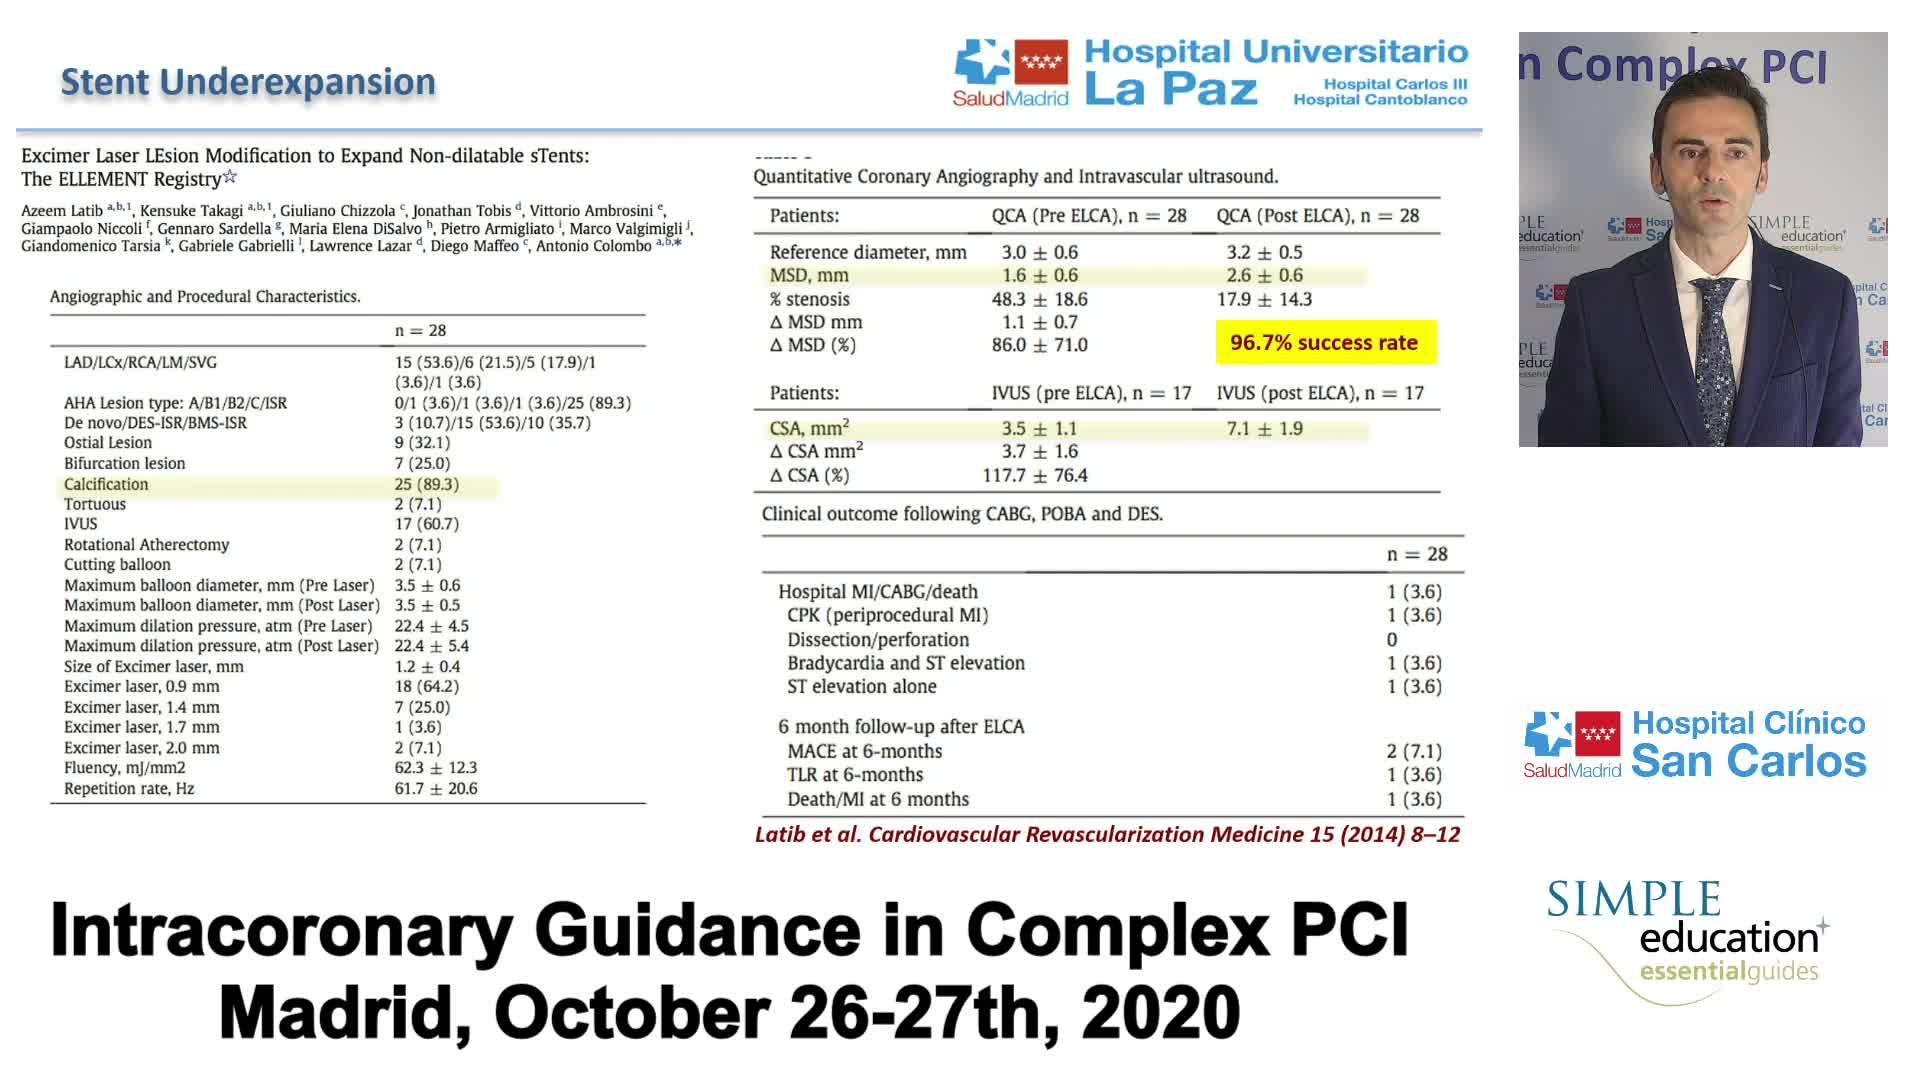

Complex PCI eCourse Madrid 26th October 2020

Complex PCI eCourse Madrid 27th October 2020

Coronary Bifurcations: An Update on Diagnosis, PCI planning and Imaging and PhysiologyGuidance - Dr Dejan Milasinovic